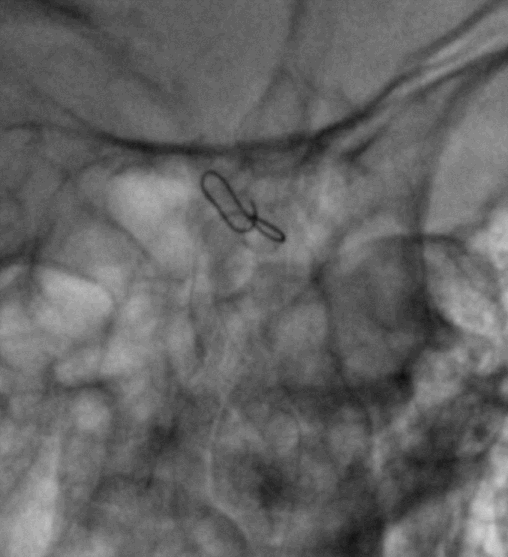

4mm×30mm Streamline

术后4月余随访:多发动脉瘤均未见显影,远端残余轻度狭窄

术前术后对比